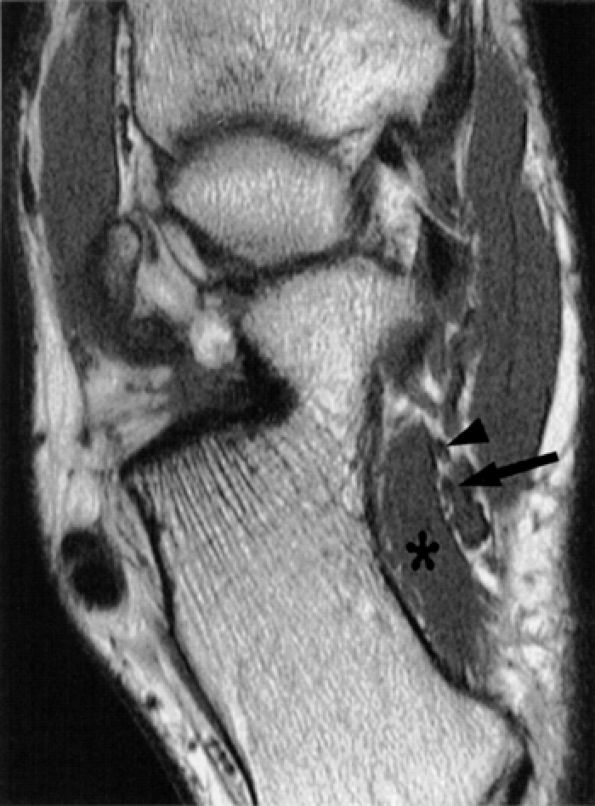

FIGURE 6.49 ● Tarsal tunnel syndrome and medial plantar nerve denervation edema due to proliferative synovitis. (A) Axial T2-weighted image demonstrates a synovial mass (asterisk) in the tarsal tunnel. (B) Sagittal T2-weighted fat-suppressed image illustrates denervation edema in the flexor digitorum brevis muscle (asterisk). Note associated osteoarthritic changes in the anterior tibiotalar joint (arrow).

|